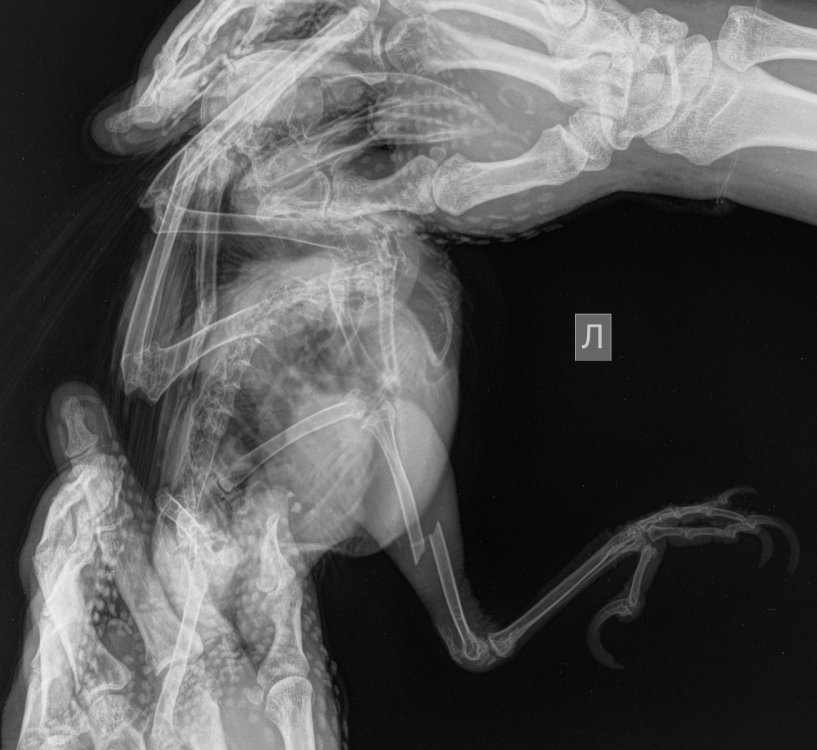

Сделан рентген, обнаружен закрытый перелом берцовой кости и наложена лангетка. На днях будем делать повторно и решать вопрос о необходимости установки спиц (остеосинтез). На шею птице одел защитный ошейник (иначе моментально начинает рвать лангетку на лапке), держится свободно туда даже палец проходит.

• даже с лангеткой ножка сильно выгибается наружу, подвижность больше чем у здоровой. я подозреваю также вывих сустава тазобедренного. как проверить ножку на вывих? это может сделать врач ощупывая или вывих можно увидть на рентгене?

Прикрепляю фото вороны, рентгена и лангетки.

Прошу специалистов прокомментировать рентген (есть однозначно видный вывих?).

241101 карлуша перелом.jpeg

если что рентген ДО наложения лангеты, сейчас как стоит кость неизвестно...